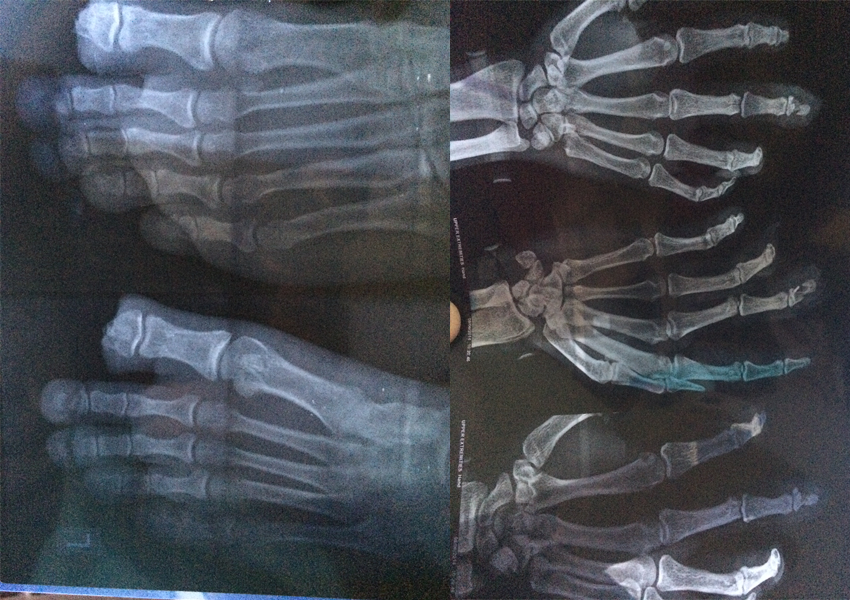

Trauma Surgery

Trauma Surgery is a surgical speciality that utilizes both operative and non-operative management to treat traumatic injuries, typically in an acute setting.